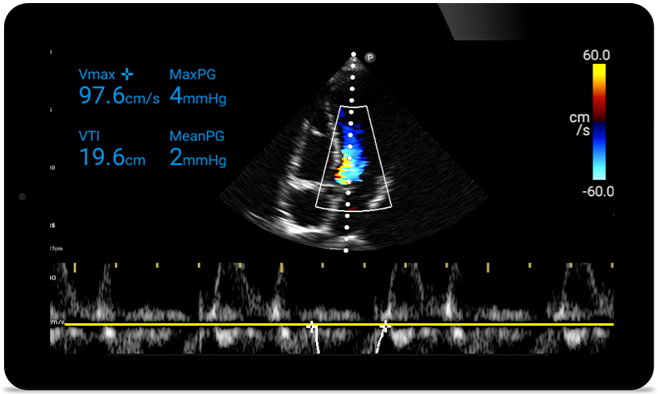

Schneller reagieren, das Herz schützen

Wenn jede Sekunde zählt, kann mobil einsetzbarer Ultraschall den entscheidenden Unterschied machen. Lumify bietet die hochauflösenden Bilder, die Sie benötigen, an jedem Ort und zu jeder Zeit.

Fallstudie

An Opportunity to potentially reverse cardiomyopathy (Möglichkeit zur potenziellen Umkehr von Kardiomyopathie)

Tutorial (Engl.)

Intro to transthoracic echocardiography (Einführung in die transthorakale Echokardiographie)